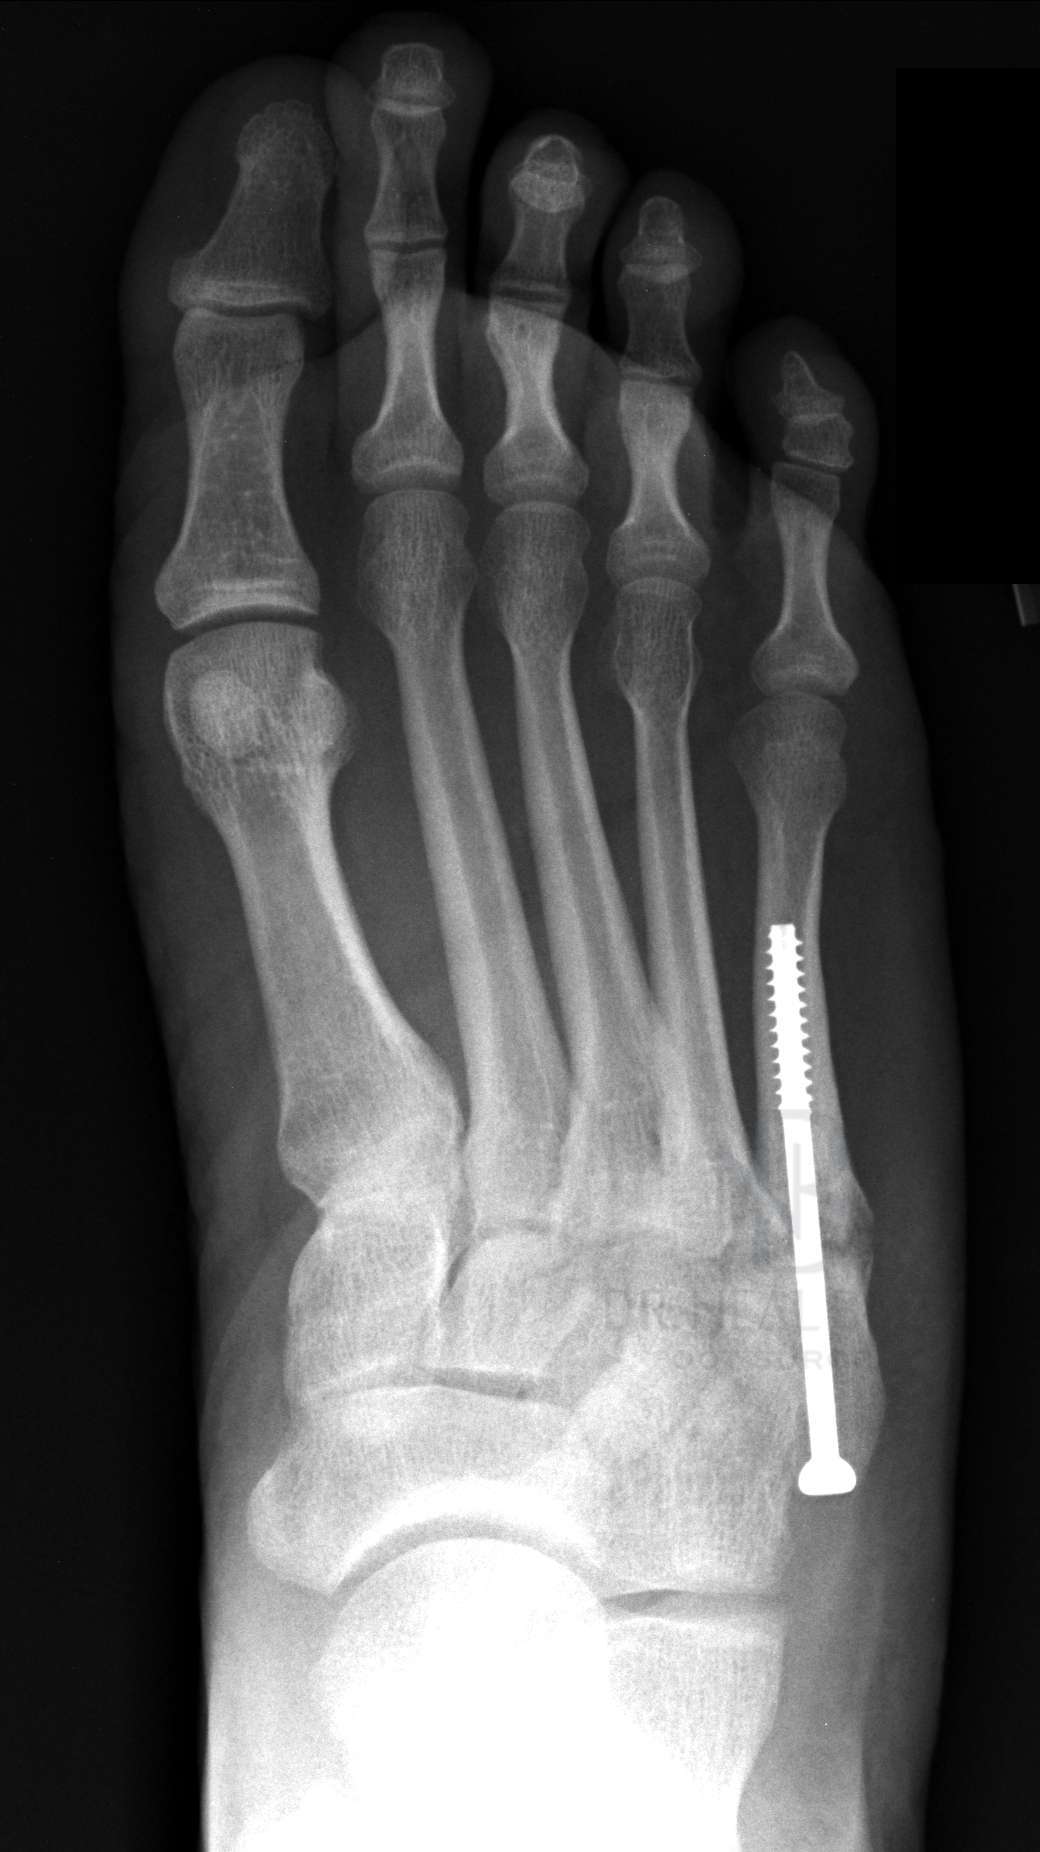

- 수술: 복합 골절이나 압박 골절의 경우에는 핀을 박는 수술이 필요할 수 있습니다.

- 금속판 사용: 뼈가 조각나거나 비스듬하게 부러진 경우에는 금속판을 덧대어 고정하기도 합니다.

- 복합 골절: 뼈가 여러 조각으로 깨져 있는 경우에는 핀이나 금속판을 사용하여 뼈를 고정해야 할 수 있습니다.

- 비스듬한 골절: 뼈가 비스듬하게 부러진 경우에도 핀을 사용하여 고정하는 것이 일반적입니다.

- 핀을 사용한 수술: 핀을 박는 수술의 경우, 핀고정 수술비용 및 입원 비용이 대략 100~150만 원 정도 나옵니다.